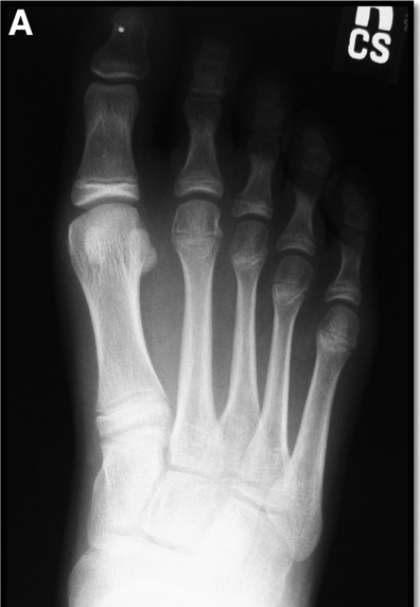

Smillie分期共有5期:

• Ⅰ期:干骺端的血供已遭破坏,出现裂缝骨折,周围松质骨开始硬化,但没有明显的外在表现;

• Ⅱ期:跖骨头中心硬化的松质骨被吸收,背侧软骨开始向跖侧塌陷,跖趾关节面的轮廓发生改变;

• Ⅲ期:随着骨质被进一步吸收,软骨继续向跖侧塌陷,但跖侧的软骨仍相对完整;

• Ⅳ期:整个跖骨头塌陷,部分关节软骨开始脱落,关节面的解剖结构已无法重建;

• Ⅴ期:跖趾关节炎明显,跖骨头已变扁平,仅跖侧的关节软骨可能仍部分保留原始的外形轮廓

病理分期与X线分期相对应

影像学表现

早期

晚期